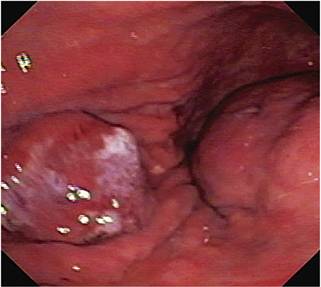

Paciente de 74 años quien ingresó por cuadro de 3 días de evolución de hematemesis y melenas, se realizó una endoscopia de vías digestivas altas y se encontró a nivel del cuerpo medio hacia la pared anterior una lesión elevada de 20 mm de diámetro con centro ulcerado, también se encontró otra lesión de aspecto subepitelial de 60 mm a nivel del antro; el diagnóstico endoscópico inicial fue elevación gástrica en estudio tipo 0-IIa/0-IIc y lesión subepitelial en un estudio (¿GIST?) (Figura 1). Se tomaron múltiples biopsias de las lesiones.